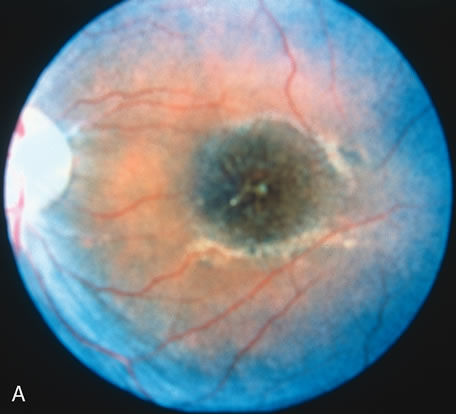

Choroideremia

In the early stages of choroideremia, before choroidal atrophy is funduscopically obvious and when the picture resembles RP, FA indicates diffuse choroidal atrophy throughout the entire retina. Only the macular area remains preserved (Fig. 4A and B).

Fig. 4. Choroideremia and choroideremia carrier. A. The choroidal atrophy in this affected male is not apparent in the fundus. B. However, the angiogram shows diffuse atrophy of the choriocapillaris with persistent visualization of the larger choroidal vessels. C. This carrier female has peripapillary choroidal atrophy and diffuse pigment mottling. D. The patchy areas of focal choroidal atrophy that occasionally occurs in carriers is evident on angiography. |